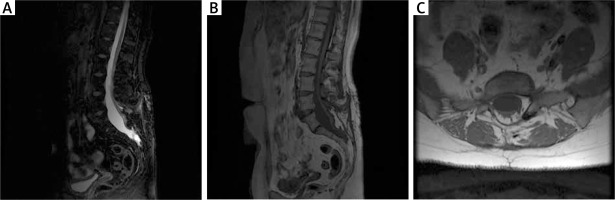

The patient had significant improvement in lower limb mobility and sphincter function. There was minimal improvement in sensation. The pain in the lumbar region remained unchanged. The patient was consulted on an outpatient basis 12 months after the surgical treatment. She did not report any recurrence of symptoms and the therapeutic effect remained good. MRI examination showed healed surgical area and subtotally removed adipose tissue (Figure 3).

Figure 3

MRI scan at 12 months after surgery in the first patient. A – T2-weighted MR imaging with a healed surgical approach area. B – T1-weighted MR imaging with variable flip; a properly healed surgical approach area. C – T1-weighted MR imaging, axial sections; healed wound with the visible laminectomy site